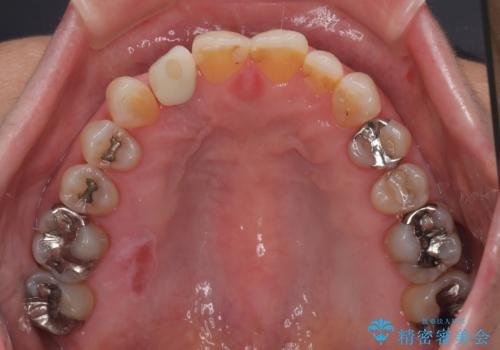

- 前歯のインプラント治療を検討して様々医院を探していたところ、1回の手術で治療ができるとのことで来院された患者様です。

長期間の治療と外科処置の回数が多くなることを懸念して、なかなかインプラント治療に乗り出せなかったそうですが、1DAYインプラントというものがあることを知り、当院にいらっしゃいました。

仮歯を事前に用意し、インプラント埋入時に即日で仮歯を装着する、即時荷重インプラントの計画で治療を進めて行くこととしました。